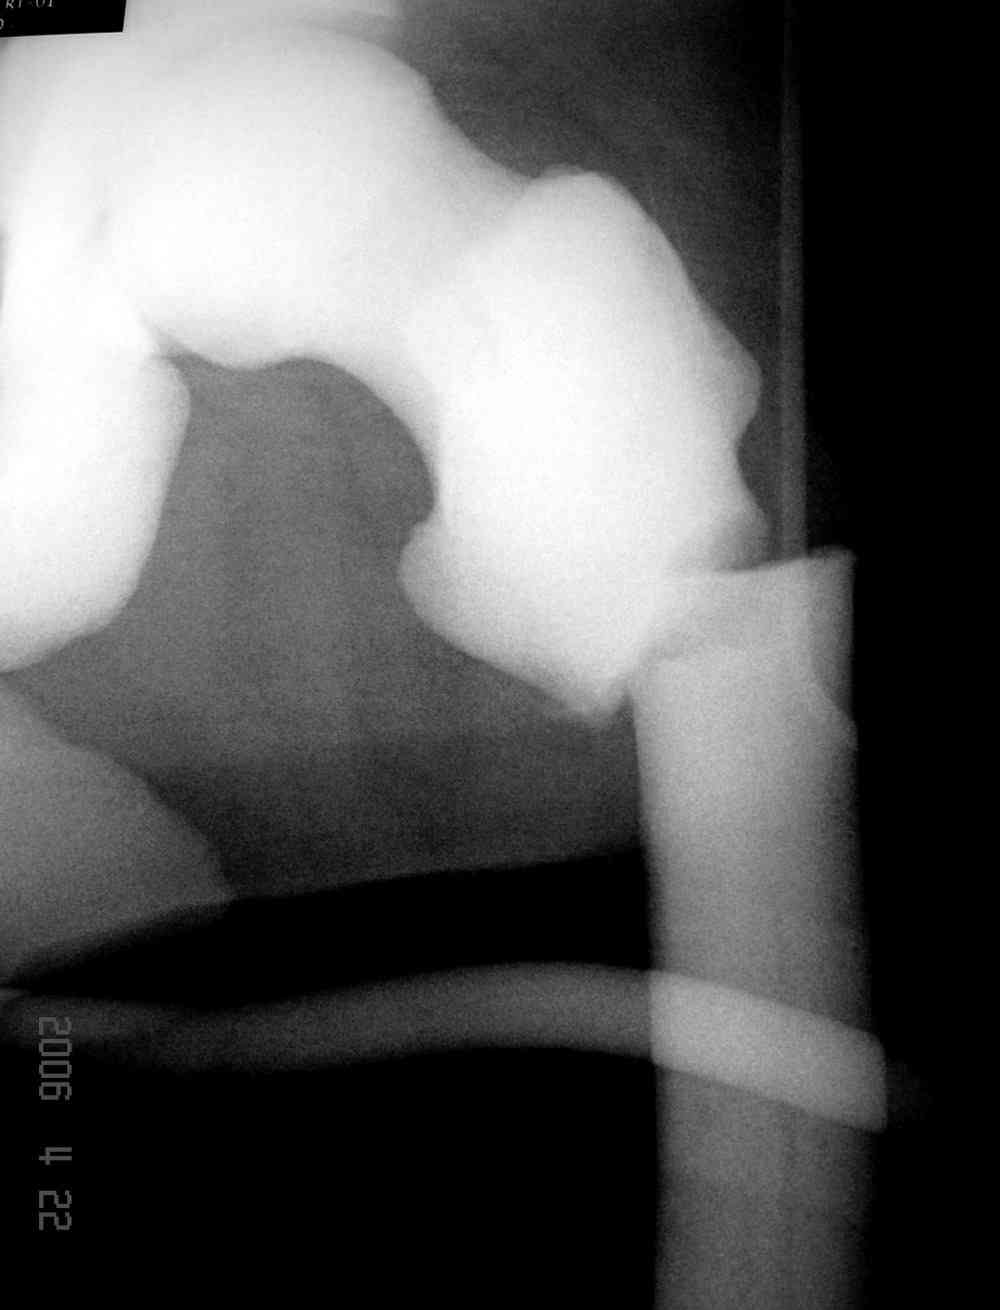

Уважаемый Константин Иванович! Полностью согласен с проф. Михайловым, данный случай не похож на мраморную болезнь, при которой имеется резкое, строго симметричное и генерализованное уплотнение костной ткани (остеопетроз), и кость оказывается построенной преимущественно из гомогенного компактного костного вещества. Для примера привожу случай из архива нашего института (бедренные, плечевые кости и таз, рис 1,2,3)

Изменения структуры костей у Вашего пациента больше похожи на полиоссальную форму фиброзной дисплазии или болезнь Педжета, возможены также инфаркты костного мозга б.берцовых костей. К сожалению, качество снимка не очень хорошее, непонятно, сохранен ли кортикальный слой б.берцовых костей по передней поверхности.

Для примера привожу случай из архива американской ассоциации рентгенологов (ACR) - развитие злокачественной фиброзной гистиоцитомы на левой б.берцовой кости у пациента с множественными инфарктами костного мозга (рис 4,5 - левая, рис 6 - правая)

Не являюсь специалистом по костной патологии, но мне кажется, на ренгенограмме множественные мета-диафизарные образования напоминяющее змееподобных извилистых линии и периостеальные ламинирование очень напоминяет картину остеонекроза (инфаркта) костей, возможно связано с длительным применением стероидов.

При предоставлении дополнительных информации, сканнирования, МРТ и лабараторных данных можно уточнить предварительный диагноз, пока склонен к обширному костному инфаркту, и таких больных рекомендуем лечить сиптоматически.

слайды из прошлегодного случая.